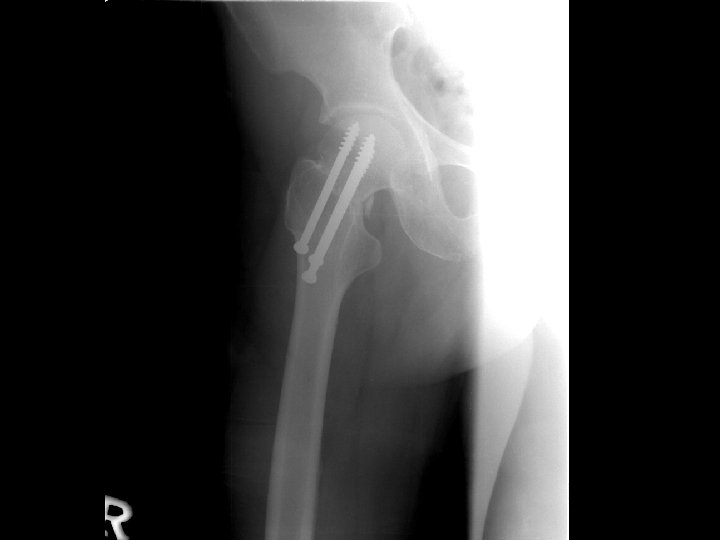

Plan n Arrange open reduction and internal fixation with three cannulated screws

Evidence-Based Medicine n n Patient : A 59 y/o female was a case of femoral neck displaced fracture, right hip Intervention : Open reduction and internal fixation Comparison : Arrangement of arthroplasty Outcome : Open reduction and internal fixation was better than arthroplasty of the outcome